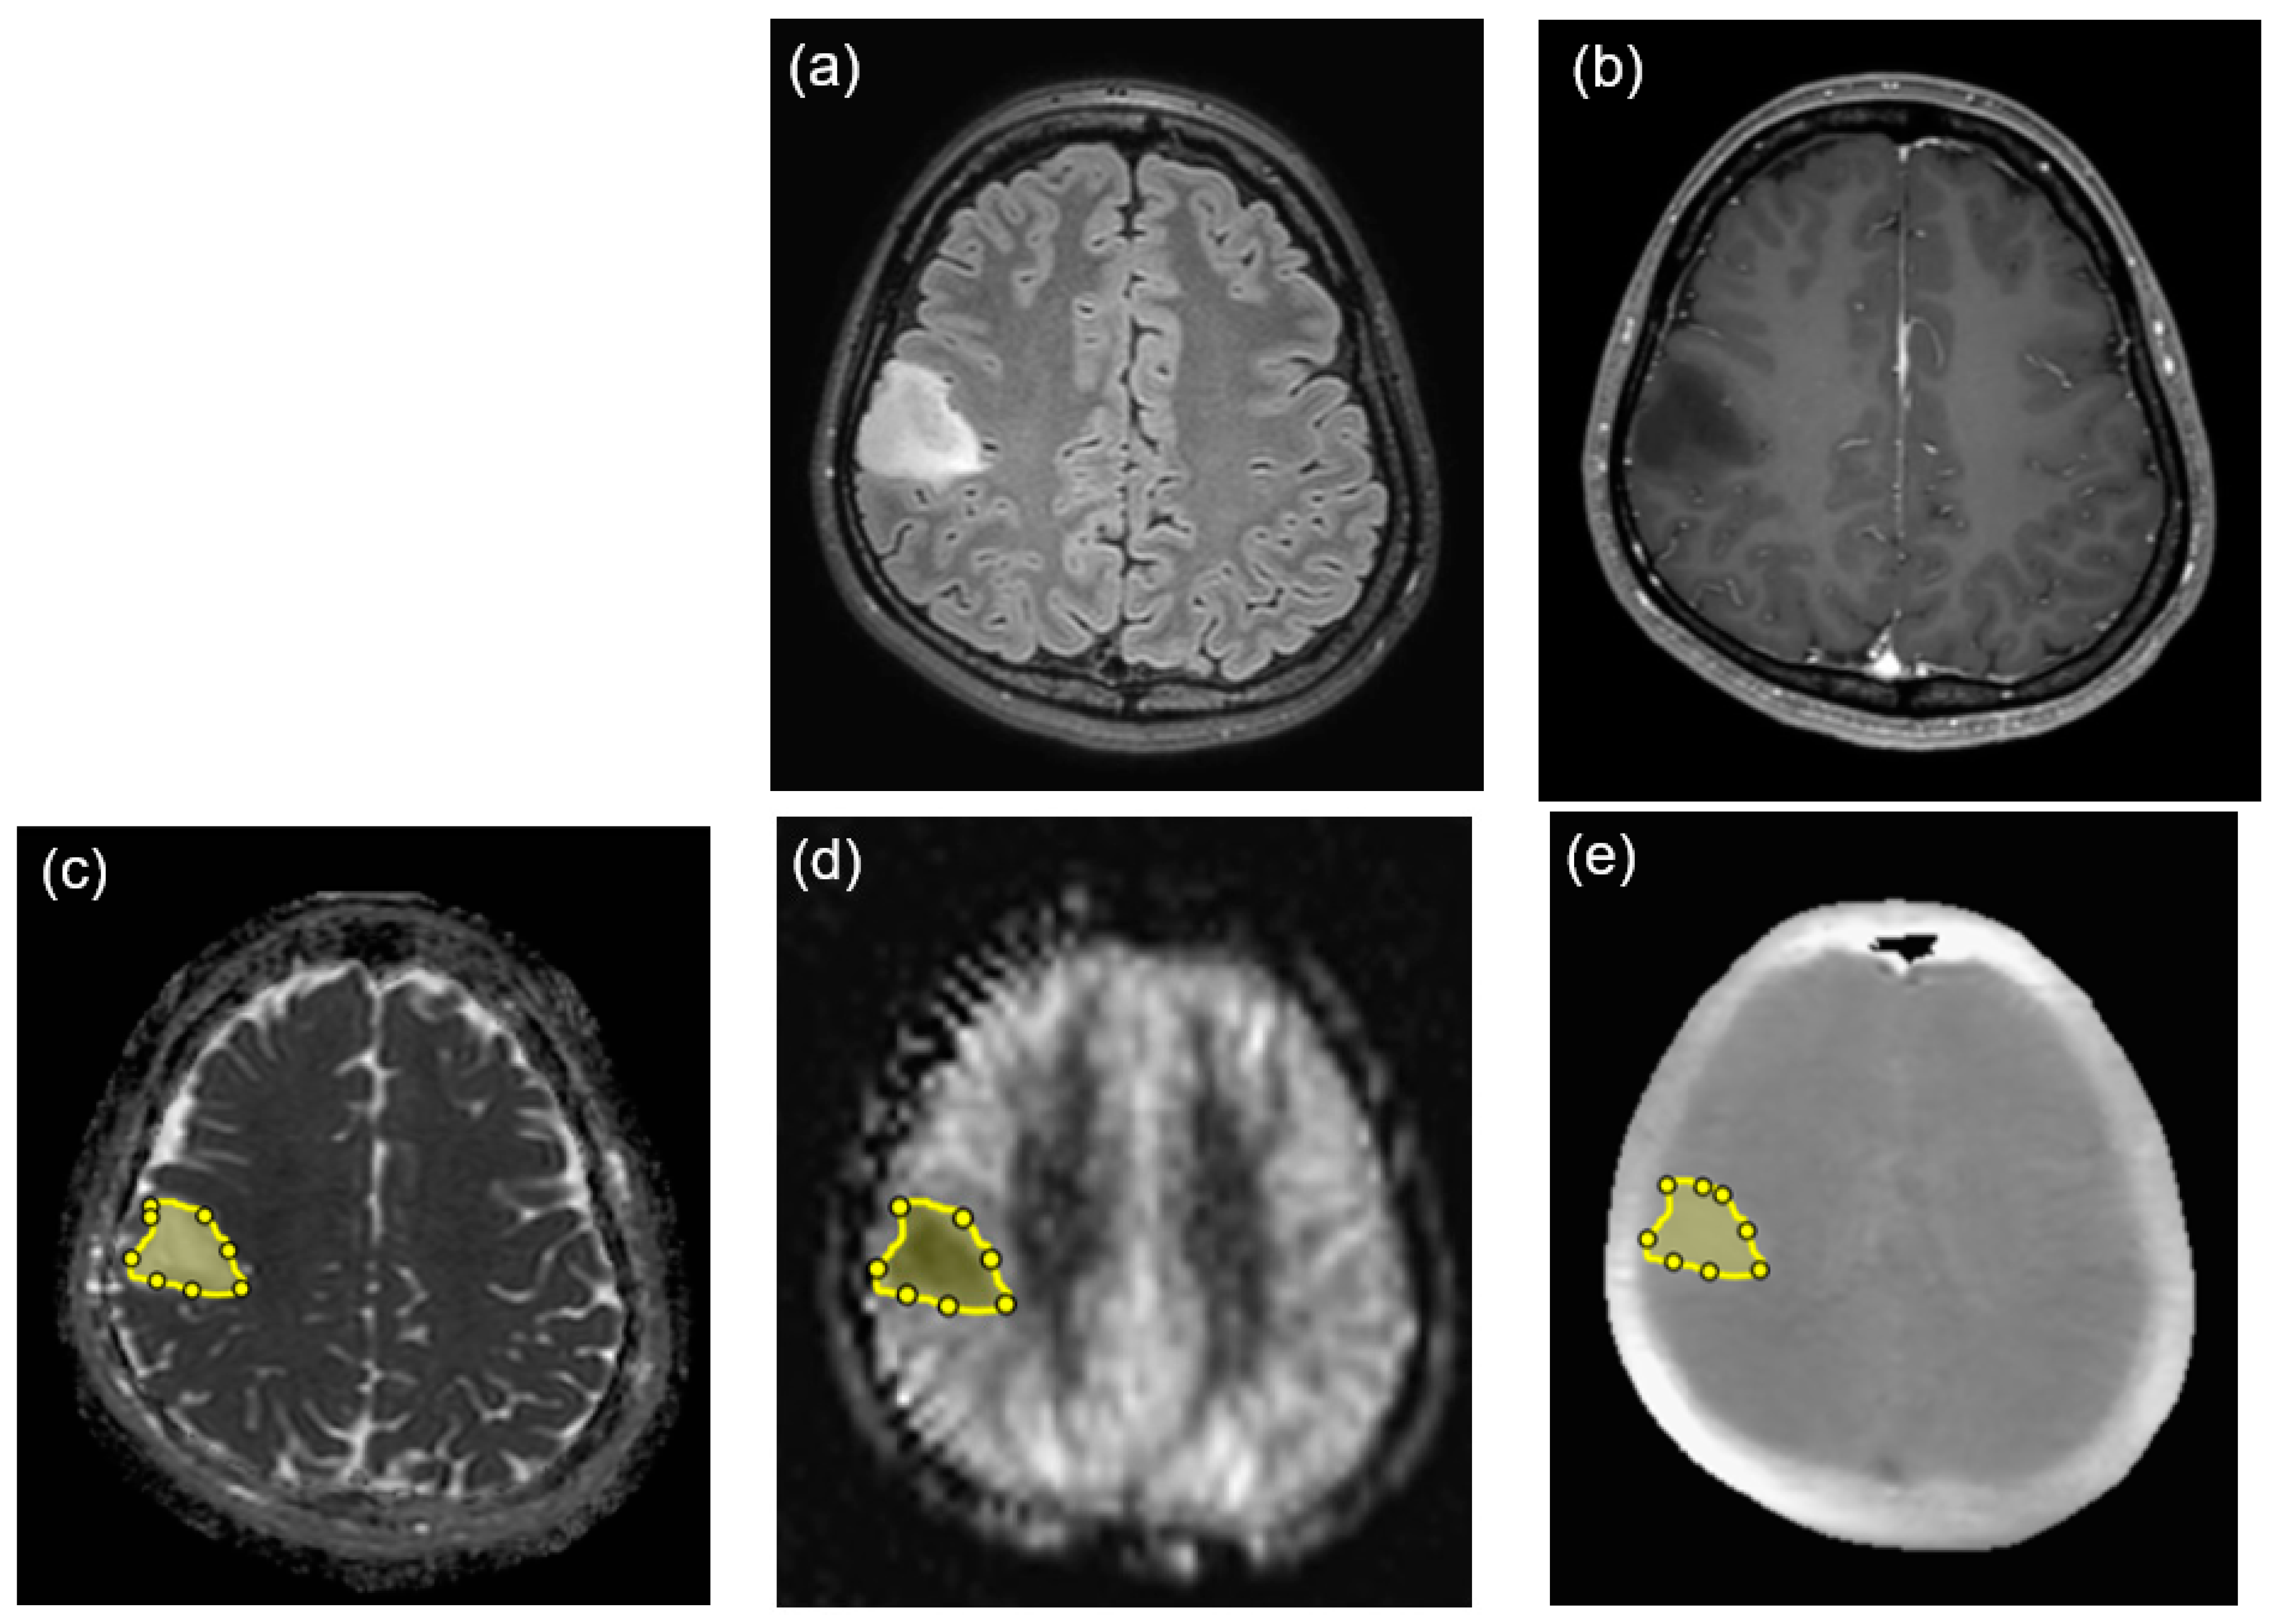

2.2. MRI Protocol

2.3. Image Analysis